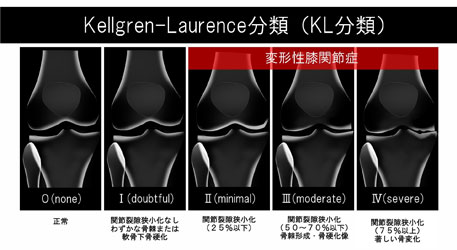

変形の重症度と痛みは関係がある

これは変形性膝関節症の「重症度」を示す指標です。 感覚的にはもちろん「変形がひどければひどいほど痛みが強い」と考えがちですが、実は

変形と痛みには関連がない

という研究結果が多数報告されています。

他にも

・40歳以上の「無症状の膝」でも、37%に変形がみられる

・Grade4(重症)の膝でも、30%は無症状である

というエビデンスも多数存在します。

つまり、いくら膝の変形が重度であったとしても

症状の改善を諦める必要はないのです。